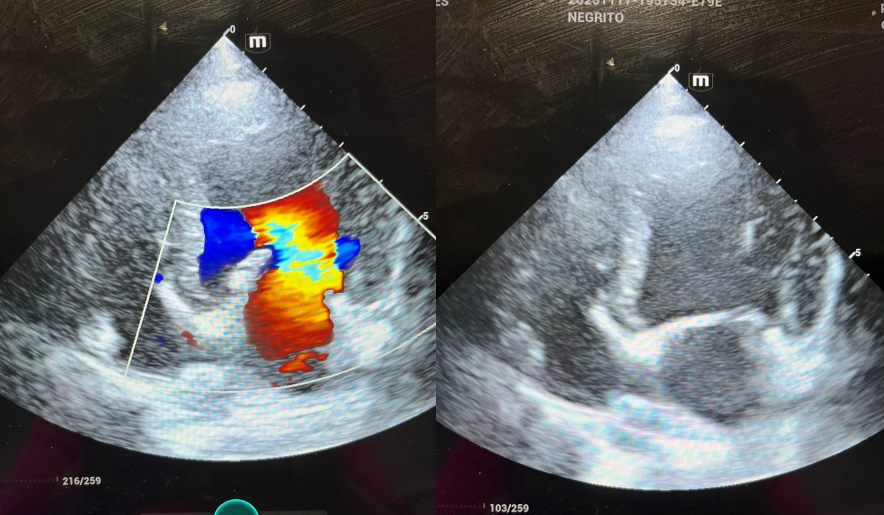

Eco-cardiografía Veterinaria

Es una evaluación detallada del corazón mediante ultrasonido. Permite diagnosticar problemas cardíacos como soplos, insuficiencia cardíaca o enfermedades congénitas. Nuestro equipo portátil permite hacerlo en tu casa sin estrés para tu mascota.